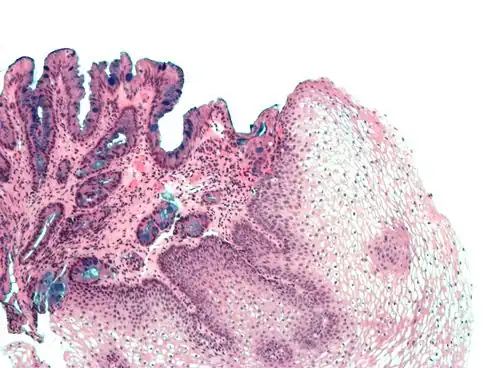

Section of the human skin showing the stratified squamous epithelial surface, referred to as the epidermis. The layer of keratin here is named the stratum corneum.

In the epidermis of skin in mammals, reptiles, and birds, the layer of keratin in the outer layer of the stratified squamous epithelial surface is named the stratum corneum. Stratum corneum is made up of squamous cells which are keratinized and dead. These are shed periodically.